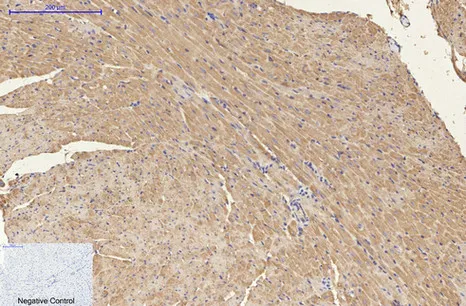

HER2(11H9)Mouse Monoclonal Antibody

Cat: AMM11986

Size1:50μL Price1:$118

Size2:100μL Price2:$220

Size3:200μL Price3:$380

Application:WB,IF-P,IF-F,ICC/IF,IHC-P

Reactivity:Human,Mouse,Rat

Conjugate:Unconjugated

Optional conjugates: Biotin, FITC (free of charge). See other 26 conjugates.

Gene Name:ERBB2